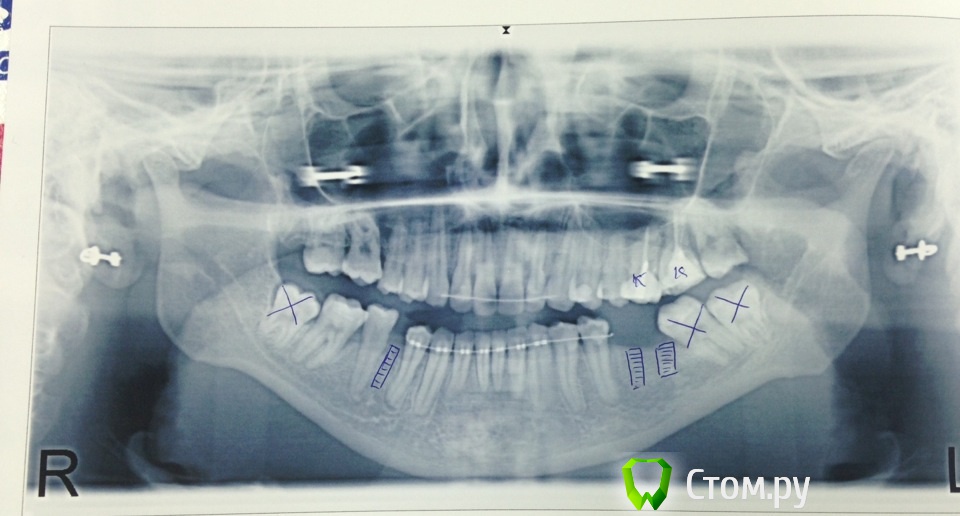

Notfake Опубликовано 11 декабря, 2013 Поделиться Опубликовано 11 декабря, 2013 (изменено) Здравствуйте, уважаемые врачи!Почти что 2 года носила брекеты, сняли ровно месяц назад, оставив ретейнеры и ничего не сказали, что делать дальше - сказали ставить импланты, а потом только лечение продолжится. Поскольку клиника находится не в моем городе, я обратилась в клинику в своем городе для лечения кариеса, появившегося после снятия брекетов. Там вылечили все что хотела, и очень напугали по поводу состояния зубов. Что срочно надо делать либо протезирование, либо имплантацию, иначе потеряю боковые зубы в нижнем ряду... В другой клинике сказали что в моем случае возможна только имплантация и никакого протезирования. На снимке крестиками показаны зубы к удалению, а заштрихованные квадратики - импланты. Снимок в день снятия брекетов был сделан. Подскажите пожалуйста, что все-таки делать и возможно ли обойтись без имплантов?((( все-таки это пока и болезненная, длительная и дорогостоящая операция...Хотела бы услышать Ваше мнение по этому вопросу, в частности по протезированию нижней челюсти импланты либо мост. Спасибо Вам за внимание... Изменено 11 декабря, 2013 пользователем Notfake Ссылка на комментарий